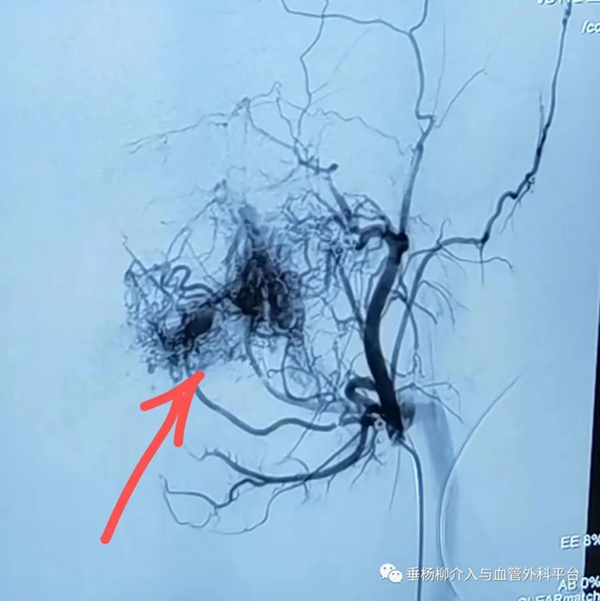

3.数字减影血管造影(digital subtraction angiography,DSA)检查可以相对全面地反映颌骨中心性血管瘤的血管构筑及血流动力情况,可以作为颌骨中心性血管瘤动诊断的“金标准”,典型表现为具有动静脉瘘口的畸形血管团块、扩张的供血动脉及静脉期提前显示的回流静脉。

左下颌中心性血管瘤DSA表现畸形的血管团块